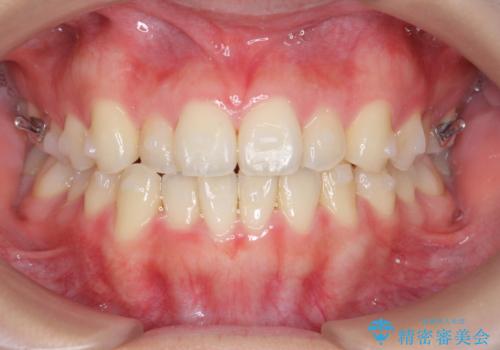

マウスピース矯正で前歯のガタつきを改善

- 上下の前歯のガタつきの改善を求めて、矯正治療を希望され来院されました。

矯正検査の結果、マウスピース矯正システム インビザラインの適応であることからワイヤーを用いず矯正治療を進めることとしました。

1日20時間以上の使用時間をきっちりと守っていただけたため、良好な治療結果、歯並びを手に入れることができました。